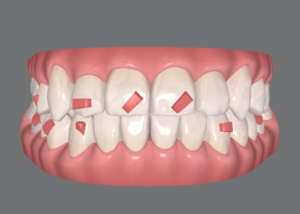

細かい私のために、院長が一生懸命練ってくださった治療計画は全11ステージです。

上の前歯には今までで一番大きなアタッチメントがドーンと付きます。

最終的には、こんな歯並びになる予定です。

何が変わったのか分かりづらいので、こちらもご覧ください!